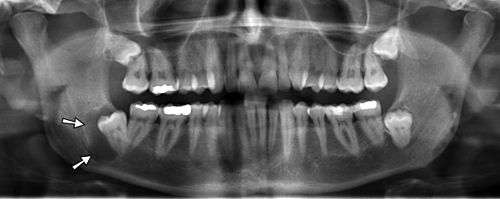

A dental panoramic radiograph, showing the maxilla and mandible, all the teeth including the "wisdom teeth," the frontal and maxillary sinuses, the nasal cavity and the temporomandibular joint and other near by head and neck anatomy. | |

A panoramic radiograph is a panoramic scanning dental X-ray of the upper and lower jaw. It shows a two-dimensional view of a half-circle from ear to ear. Panoramic radiography is a form of tomography; thus, images of multiple planes are taken to make up the composite panoramic image, where the maxilla and mandible are in the focal trough and the structures that are superficial and deep to the trough are blurred.